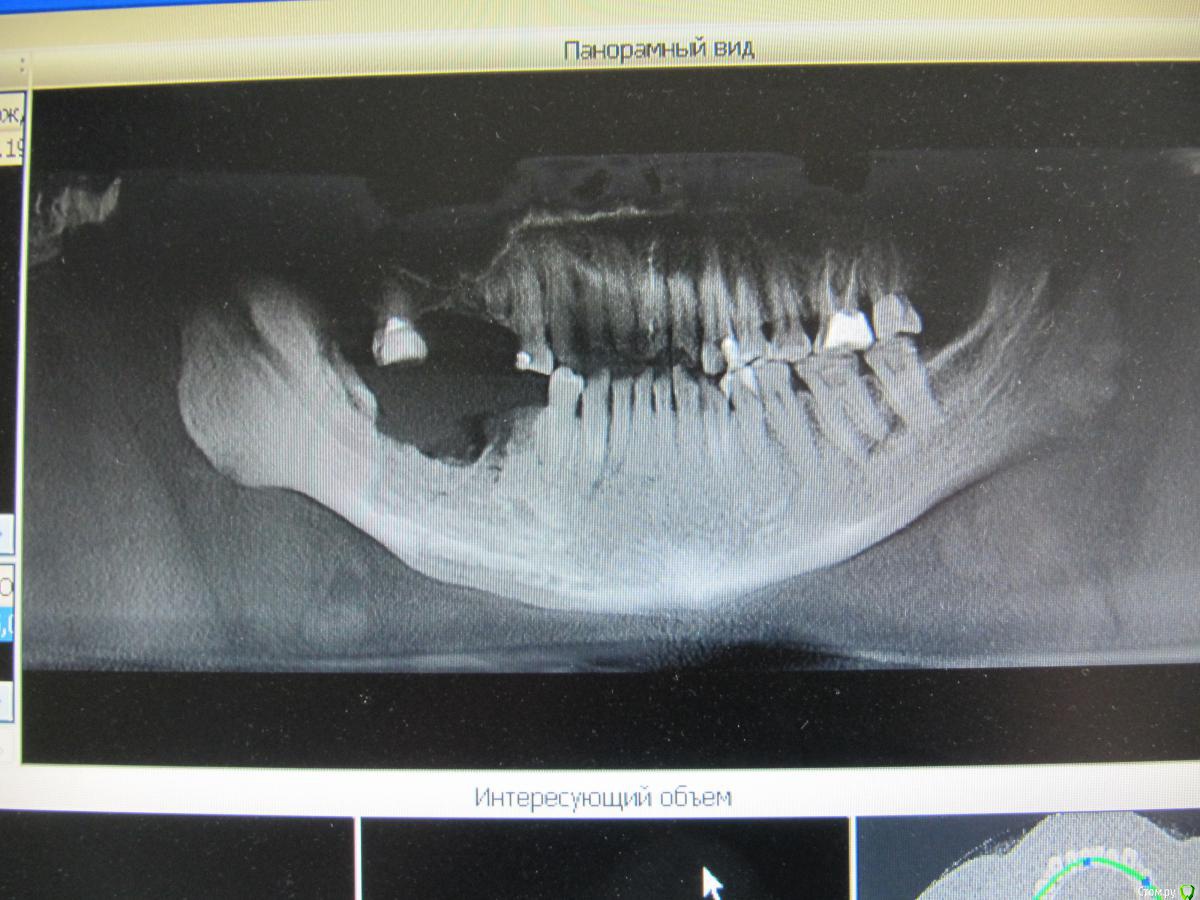

Alexey Doc Опубликовано 14 марта, 2015 Поделиться Опубликовано 14 марта, 2015 Поделюсь своим скромным опытом:Первый раз встретился с подобной проблемой 3 года назад: Онкологическая больная получающая терапию золедроновой кислотой в течение 7 месяцев обратилась с жалобами на ноющие боли в области нижней челюсти справа и незаживающие лунки зубов 4.5, 4.6 ( которые и были удалены в поликлинике месяц назад как причина этих болей ). Вел эту больную в течение 2-х лет - за это время удалил 2 секвестра. Передал больную коллеге в связи с переездом в другой город. Вот откопал её панорамную реконструкцию КТ Вторая больная обратилась полгода назад с жалобами на боли в области зуба 3.8. В анамнезе множественная миеломная болезнь, терапия золедроновой кислотой в течение 2-х месяцев. Возможностей для сохранения зуба не было. Выполнено атравматическое удаление с ушиванием лунки, заживало без особенностей первичным натяжением. Рекомендована санация полости рта. На осмотр больше не появлялась. Звонил через 2 месяца после удаления - сказала что все хорошо в случае чего сообщит, жду... Думаю что все должно быть хорошо, как то успокаивает что препарат на момент удаления только начала принимать, а там посмотрим 3 Ссылка на комментарий

kriokov Опубликовано 10 октября, 2024 Автор Поделиться Опубликовано 10 октября, 2024 (изменено) Случай из практики , поделился коллега. Пациентке в 2019 году установлены имплантаты и НКР. В 2022 обнаружена злокачественная опухоль молочной железы. В дальнейшем метастазы в позвоночник, терапия , в том числе и бифосфонатами. Коллега делал осмотр и реннтгенографию в 2022, с его слов на снимках была убыль кости в области имплантата 37 на два витка. На сегодня жалобы пациентки- боли , особенно в вечернее время. Пациентка лечиться у онкологов с применением бифосфонатов. Изменено 10 октября, 2024 пользователем kriokov неправильно вставил ОПТГ Ссылка на комментарий